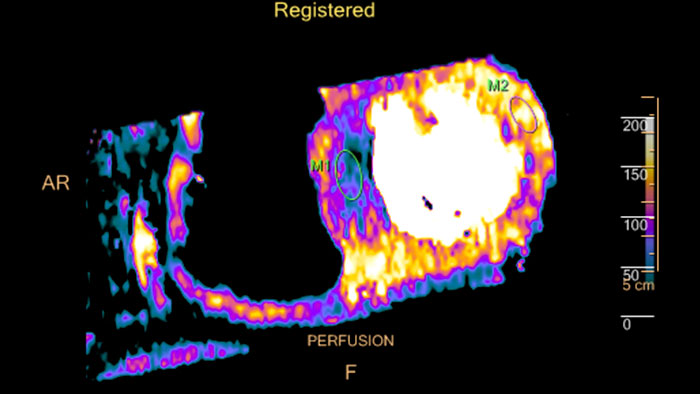

Fusing cardiac CT-MI images

Cardiac CT-MI Fusion incorporates support for myocardial perfusion imaging (MPI).

un-gated stress MI datasets simultaneously with the CT.

Dynamic color maps provide an assessment of myocardial risk

Provides automatic and manual tools to help visualize and assess signal intensity differences (in Hounsfield Unit) focusing on the left ventricular myocardium, providing quantitative myocardial perfusion measurements for CT images.

Evaluate fused coronary anatomy

Emory Cardiac Toolbox (ECTb) HeartFusion offers fusion of a patient’s coronary tree from cardiac CT angiography with MI perfusion images.